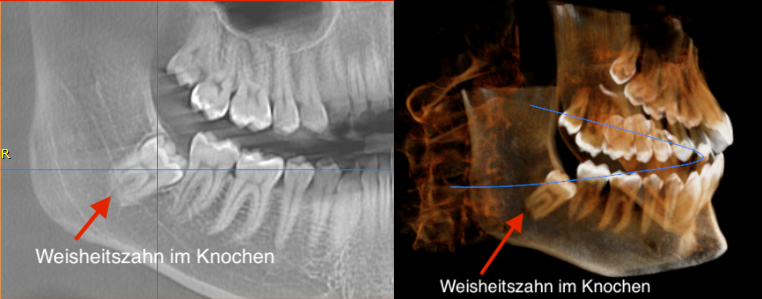

Sie können notwendig werden bei tief beschädigten, kariösen Zähnen oder bei nicht durchgebrochenen, retinierten Zähnen, d.h. solchen, die noch unter dem Zahnfleisch im Knochen liegen. Meistens handelt es sich bei letzteren um Weisheitszähne, jedoch auch Eckzähne oder kleine Backenzähne können „retiniert“ bleiben. Ab dem 30. Lebensjahr kann jeder nicht durchgebrochene Zahn ein Entzündungsherd im Körper sein. Oft verursachen Weisheitszähne jedoch schon früher Beschwerden und müssen daher entfernt werden.

Die digitale Volumentomographie (DVT) ist ein dreidimensionales, bildgebendes Tomographie-Verfahren. Im Vergleich zur Computertomographie (CT) wird eine wesentlich strahlenärmere Technik verwendet.

Die CT nimmt jeweils einzelne Scheiben des Körpers auf, die anschließend als Volumen zusammengesetzt werden. Die DVT Aufnahme dagegen kann direkt ein Volumen in einem Durchlauf aufnehmen. In dieser einen Aufnahme sind sämtliche Grunddaten enthalten, die über eine hochmoderne Software verschieden aufbereitet werden können. Es lassen sich präzise Bilder zur Diagnose und effektiver Behandlung im 3-D-Format herstellen.

Die Vorteile der DVT im Vergleich zum Panoramaröntgen sind die dreidimensionale Darstellung, d.h. die räumliche Darstellung des Kiefers sowie die wesentlich geringere Strahlenbelastung im Vergleich zur CT.

Die DVT mit ihrer 3D-Visualisierung ermöglicht den Kiefer- und Gesichtsknochen, Kiefergelenke, Kieferhöhlen, Zähne, Nervenverläufe und Zahnwurzeln bis ins kleinste Detail abzubilden, zu vermessen und bewerten.

Sie dient als wichtige Dateninformation für die computergestützte Chirurgie- und Implantatplanung. Höhe, Breite und Tiefe des Kieferknochens lassen sich zum Beispiel nur über die digitale 3D-Röntgendiagnostik ganz exakt bestimmen. Sensible Strukturen wie der Unterkiefernerv und der Kieferhöhlenboden im Oberkiefer können dreidimensional genau ausgemessen und somit geschont werden.

Veränderungen und Entzündungen der Nasennebenhöhlen, wie sie oft im Zusammenhang mit einer entzündeten Wurzelspitze auftreten.

Verlagerte Weisheitszähne und entzündetes Kieferknochengewebe können auf den dreidimensionalen DVT-Aufnahmen genau untersucht werden.

Durch den Einsatz der Volumentopographie lässt sich die Anzahl und Ausrichtung der Wurzelkanäle sowie die Position und Ausdehnung von Tumoren und Zysten besser darstellen.